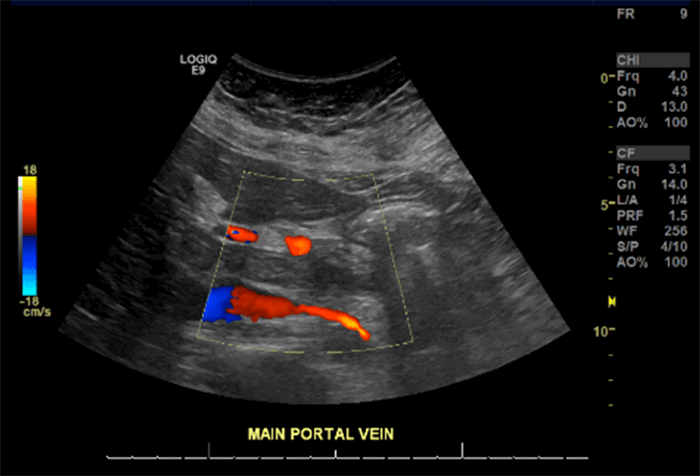

A 46-year-old morbidly obese African American woman presented with abdominal pain 13 days postlaparoscopic sleeve gastrectomy. Her pain was central and sharp in quality. She denied nausea, vomiting, or change in bowel habits. She also denied fever, chills, or dysuria. She was afebrile, hemodynamically stable, and her body mass index was 42.92. She had diffuse tenderness to deep palpation but did not exhibit peritoneal signs on exam. Labs were pertinent for mild leukocytosis, but electrolytes, blood urea nitrogen, and creatinine were within normal limits. Computed tomography (CT) of the abdomen and pelvis (Figure 1 and Figure 2) were suggestive of extensive portal vein thrombosis (PVT) that was confirmed with a follow-up ultrasound doppler study showing no flow in both branches as well as in the main portal vein (Figure 3 and Figure 4).

Figure 4. Color-flow doppler of main portal vein showing no flow.